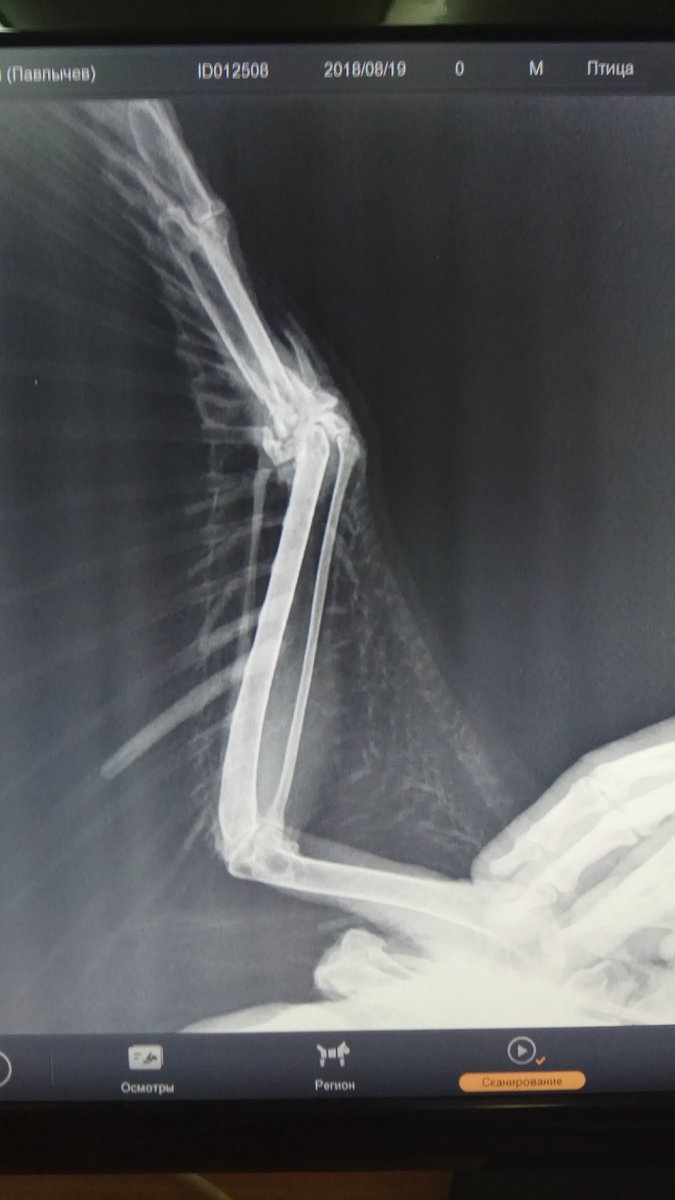

Рентгеновский снимок крыла птицы: анатомия и исследование